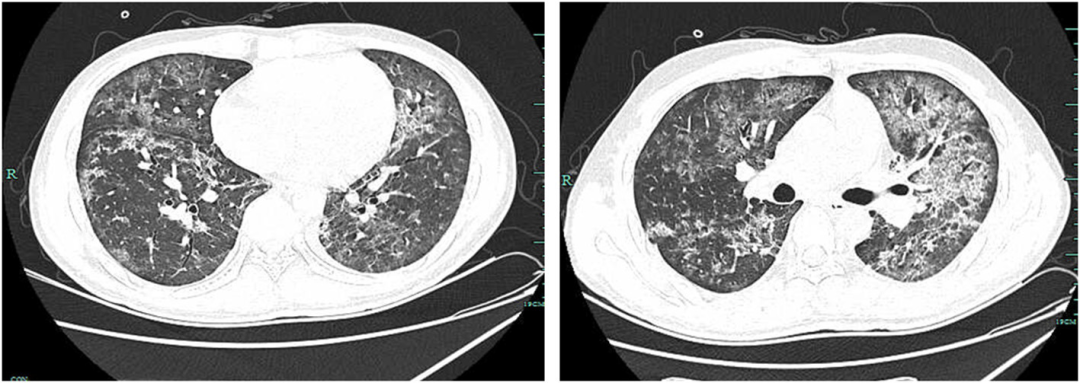

• 治疗5天后(第6天),肺部CT显示病情比治疗前更严重(图4)。NGS的结果回报耶氏肺孢子菌特异性序列数为205658,覆盖度为1.70%,TW特异性序列数为 115,覆盖度为1.00%。qPCR显示TW的拷贝数为11717.3拷贝/ml

图4:肺部CT提示双肺发生多发感染,第6天存在散在弥漫性斑片状、磨玻璃样、高密度影